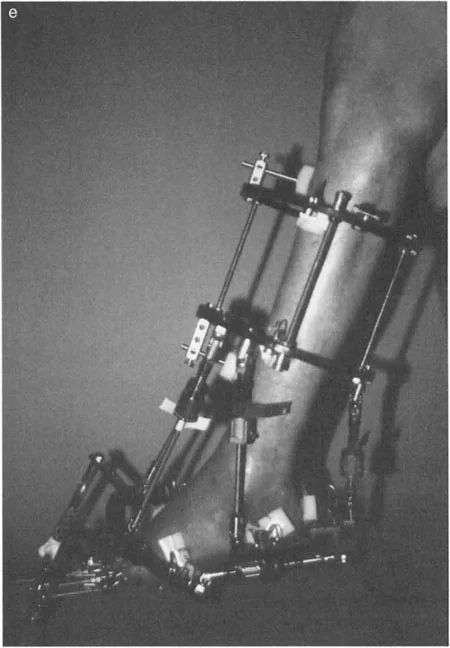

إزالة النتوءات العظمية وتعميق التلم الكاحلي

في حالات تقوس الكاحل الناتجة عن اصطدام عظمي (Bony Impingement) بسبب نتوءات عظمية في حافة الظنبوب الأمامية أو في التلم الظهري لعظم الكاحل، يقوم الأستاذ الدكتور محمد هطيف بإزالة هذه النتوءات وتعميق التلم الكاحلي للسماح لعظم الكاحل بالثني للأعلى بحرية.

* صورة توضح النتوءات العظمية التي تسبب اصطدامًا في الكاحل.

عند وجود تشوهات عظمية مثل تقوس الظنبوب البعيد، قد يتطلب الأمر قطع العظم وإعادة توجيهه. على سبيل المثال، يمكن إجراء قطع عظم قبة ظهرية (Dorsiflexion focal dome osteotomy) في الظنبوب البعيد لتصحيح انحنائه.

تحرير الأنسجة الرخوة (Soft Tissue Release)

إذا لم يتم تحقيق التصحيح الكامل بعد تطويل وتر العرقوب، قد يكون هناك حاجة لتحرير إضافي للأنسجة الرخوة، بما في ذلك اللفافة العميقة الخلفية، وتحرير المحفظة، وتفكيك الالتصاقات داخل المفصل.

- تحرير النفق الرسغي (Tarsal Tunnel Release): يُوصى به وقائيًا في تصحيحات التقوس التي تزيد عن 10 درجات، لتقليل خطر إصابة العصب الظنبوبي الخلفي والأوعية الدم